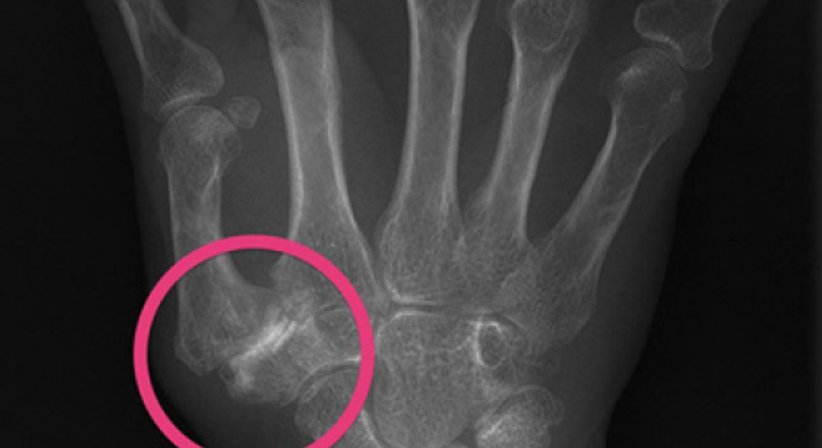

Bei der Untersuchung lässt sich über dem Daumensattelgelenk ein deutlicher Druckschmerz auslösen. Gesichert wird die Diagnose durch eine Röntgenaufnahme des Handgelenks.